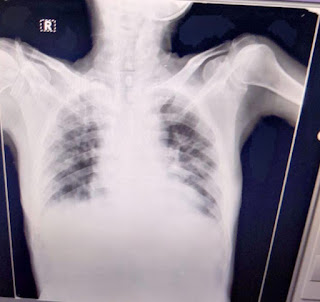

Then the patient was shifted to another local hospital where a chest X Ray was done and he was told he has viral pneumonia of the right lung.

Respiratory system:  inspection:

trachea central in position.

On auscultation:bilateral air entry present

B/L Crepititions heard, NVB

On percussion:dullness on right upper lobe,

Chest X-ray